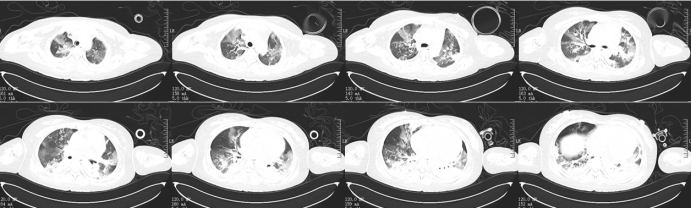

9月23日在ECMO支持下带患者外出行胸部CT检查:上肺渗出影斑片影双下肺实变,左下肺实变更明显(图7)

图片

7  患者胸部CT(2024-09-23)

928日外出复查胸部CT:双肺渗出和实变明显吸收改善(图10,图11)

10  复查胸部CT(2024-09-29)

11  患者胸部CT对比